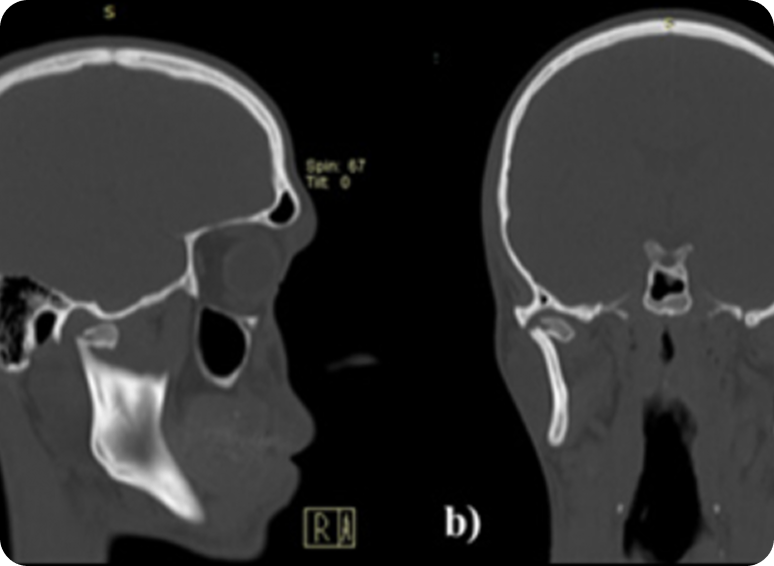

Mediante una tomografía logramos una imagen precisa para garantizar el diagnóstico.